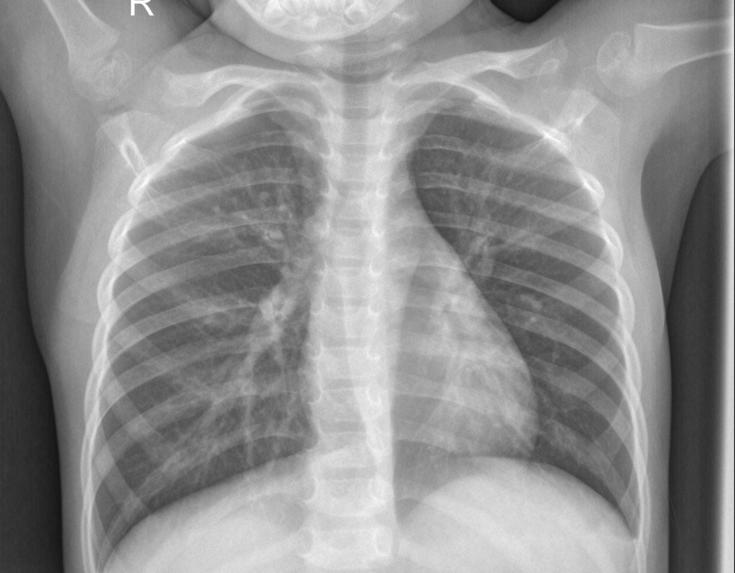

Pneumonia is a respiratory infection caused by bacteria or viruses, it affects many individuals, especially in developing and underdeveloped nations, where high levels of pollution, unhygienic living conditions, and overcrowding are relatively common, together with inadequate medical infrastructure. Pneumonia causes pleural effusion, a condition in which fluids fill the lung, causing respiratory difficulty. Early diagnosis of pneumonia is crucial to ensure curative treatment and increase survival rates. Chest X-ray imaging is the most frequently used method for diagnosing pneumonia. However, the examination of chest X-rays is a challenging task and is prone to subjective variability. In this study, we developed a computer-aided diagnosis system for automatic pneumonia detection using chest X-ray images. We develop a deep learning approach to detect pneumonia disease detection using 3 neural network algorithms CNN with vgg16, CNN with resnet50, Unet. We create a Real Time Application Pneumonia Prediction Web App using Python – Flask Framework, Deployed in Heroku Cloud Application platform.

Pneumonia remains a significant public health concern globally, contributing to substantial morbidity and mortality, particularly among vulnerable populations. Timely and accurate diagnosis of pneumonia is crucial for effective patient management and improved clinical outcomes. However, existing diagnostic methods, such as manual interpretation of X-ray images by radiologists, are often subjective, time-consuming, and prone to errors. This presents a pressing need for the development of a robust and automated system for pneumonia detection.

The objective of this project is to develop a cloud-based application powered by deep learning algorithms capable of accurately detecting pneumonia from X-ray images. The application will enable healthcare professionals to upload X-ray images securely to the cloud platform, where they will undergo automated analysis using advanced machine learning techniques. The diagnostic results, including the presence or absence of pneumonia and any associated findings, will be provided to users in a timely manner through an intuitive and user-friendly interface.